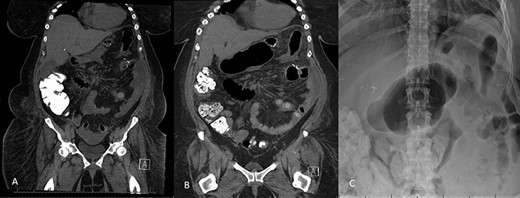

Decision was made to explore and attempt to excise the infarcted omentum. She was taken to the operating room and underwent a diagnostic laparoscopy. However, due to the large size of the omental infarction with an encapsulated necrotic liquefied, purulent secretion and significant adhesions, we decided to convert it to a midline laparotomy. We then proceeded with resection of right-sided infarcted, necrotic, liquefied omentum and abdominal washout (Fig. 3). Culture from the purulent secretion that was inside encapsulated omentum grew Streptococcus anginosus. She received Meropenem and Fluconazole. She had a prolonged and protracted recovery with a transient kidney injury and the development of multiple intra-abdominal (inter-loop, peri-hepatic, peri-splenic and pelvic) fluid collections (Fig. 4A). These collections were treated by percutaneous drainage (pelvis × 1, perisplenic and left-sided collections × 2). Three weeks from the take back, she developed a small bowel obstruction with significant dilation of the biliopancreatic limb and excluded stomach (Fig. 4B and C). She was taken to the operating room and had an endoscopically placed nasogastric tube just passed the jejunojejunostomy. Then, she underwent CT-guided gastrostomy tube to decompress in the gastric remnant (Fig. 5 A and B). One week after the rendezvous nasogastric and gastric remnant decompression, an oral and through the G-tube contrast study demonstrated patency of the gastrojejunostomy and resolution of the small bowel obstruction (Fig. 6). The patient was discharged home on POD #39 tolerating a regular postbariatric surgery diet.

A: Abdominal and pelvic CT scan obtained at POD # 29. From index RYGB and POD # 8 from excision of infarcted omentum showing loculated perisplenic, pelvic and perihepatic fluid collections. B and C: Abdominal and pelvic CT scan obtained at POD # 20 from take back and plain X-ray showing gaseous distention of the excluded stomach and duodenum, confirming a small bowel obstruction of the biliopancreatic limb.